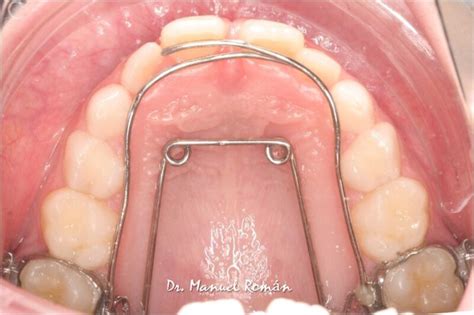

- Tratamiento: Cirugía a colgajo cerrado y tracción ortodóncica con ballesta y Tip-Edge.

- Resultados: Buenos resultados dentarios, oclusales y faciales.